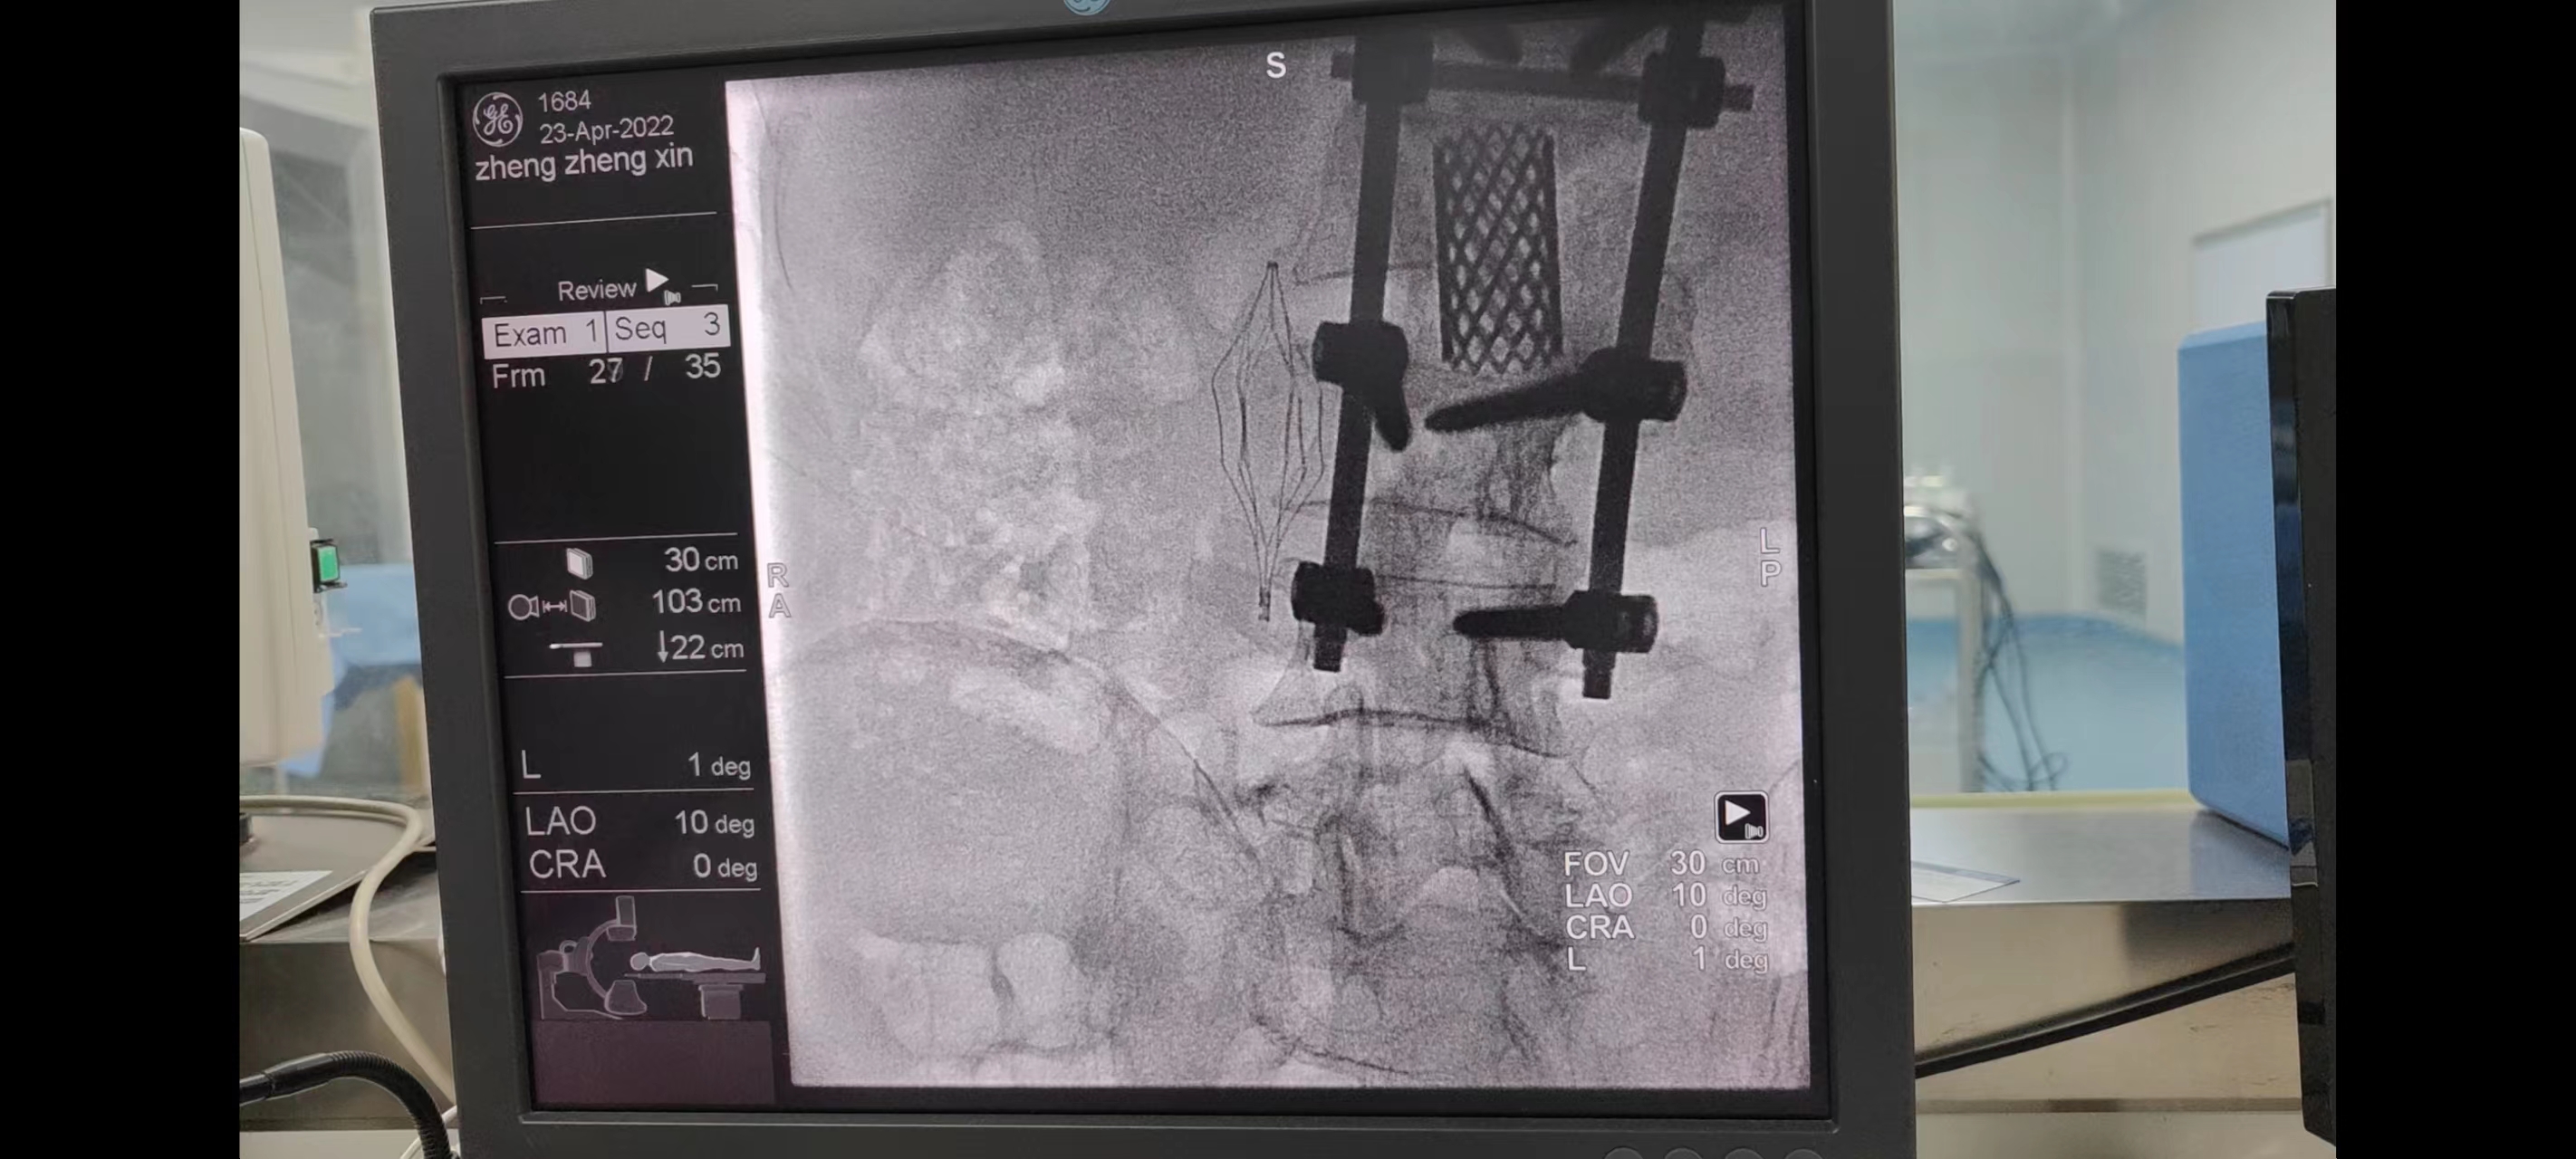

2022年04月23日经过讨论后考虑到患者年龄因素,滤器如长期置留可诱发下腔静脉闭塞、穿孔等潜在风险,本着能取则取的原则决定施行“下腔静脉滤器取出术”,在国药东风总医院李春华教授的指导下,下腔静脉滤器已被顺利取出,下腔静脉滤器见长约1cm大小血栓附着,下肢静脉造影检查静脉血栓恢复良好,血运通畅,整个手术从开始至手术完毕约38分钟,为患者解除了“滤器”异物在体内长期存在的后顾之忧,也有效拦截下肢深静脉血栓,为我院围术期管理保驾护航,增加了手术安全性,降低了术后并发症的发生,挽救患者因血栓脱离导致急性致死性肺栓塞危及生命的风险。